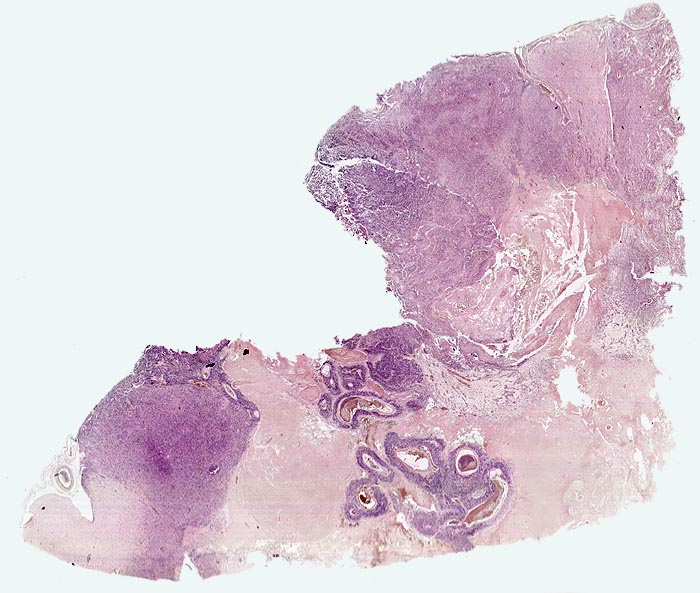

PathoPic – image database / PathoPic ID 5197 - Glioblastoma multiforme (WHO IV)

Glioblastoma multiforme (WHO IV)

maligner Tumor

Topographie

Hirn temporal

Nervensystem

Das Tumorgewebe erscheint aufgrund seiner Zelldichte blau. Die Grenze zum Hirnparenchym ist unscharf. In der Übersicht sind flächenhafte ischämische Tumornekrosen infolge einer ungenügenden Sauerstoffversorgung. Im Zentrum der Nekrose sind thrombosierte Gefässe umgeben von einem schmalen blauen Saum vitaler Tumorzellen erkennbar.

Seit zwei Monaten zunehmende Persönlichkeitsveränderungen, Kopfschmerzen und progrediente fokal neurologische Zeichen.

Histologie

Vergrösserung